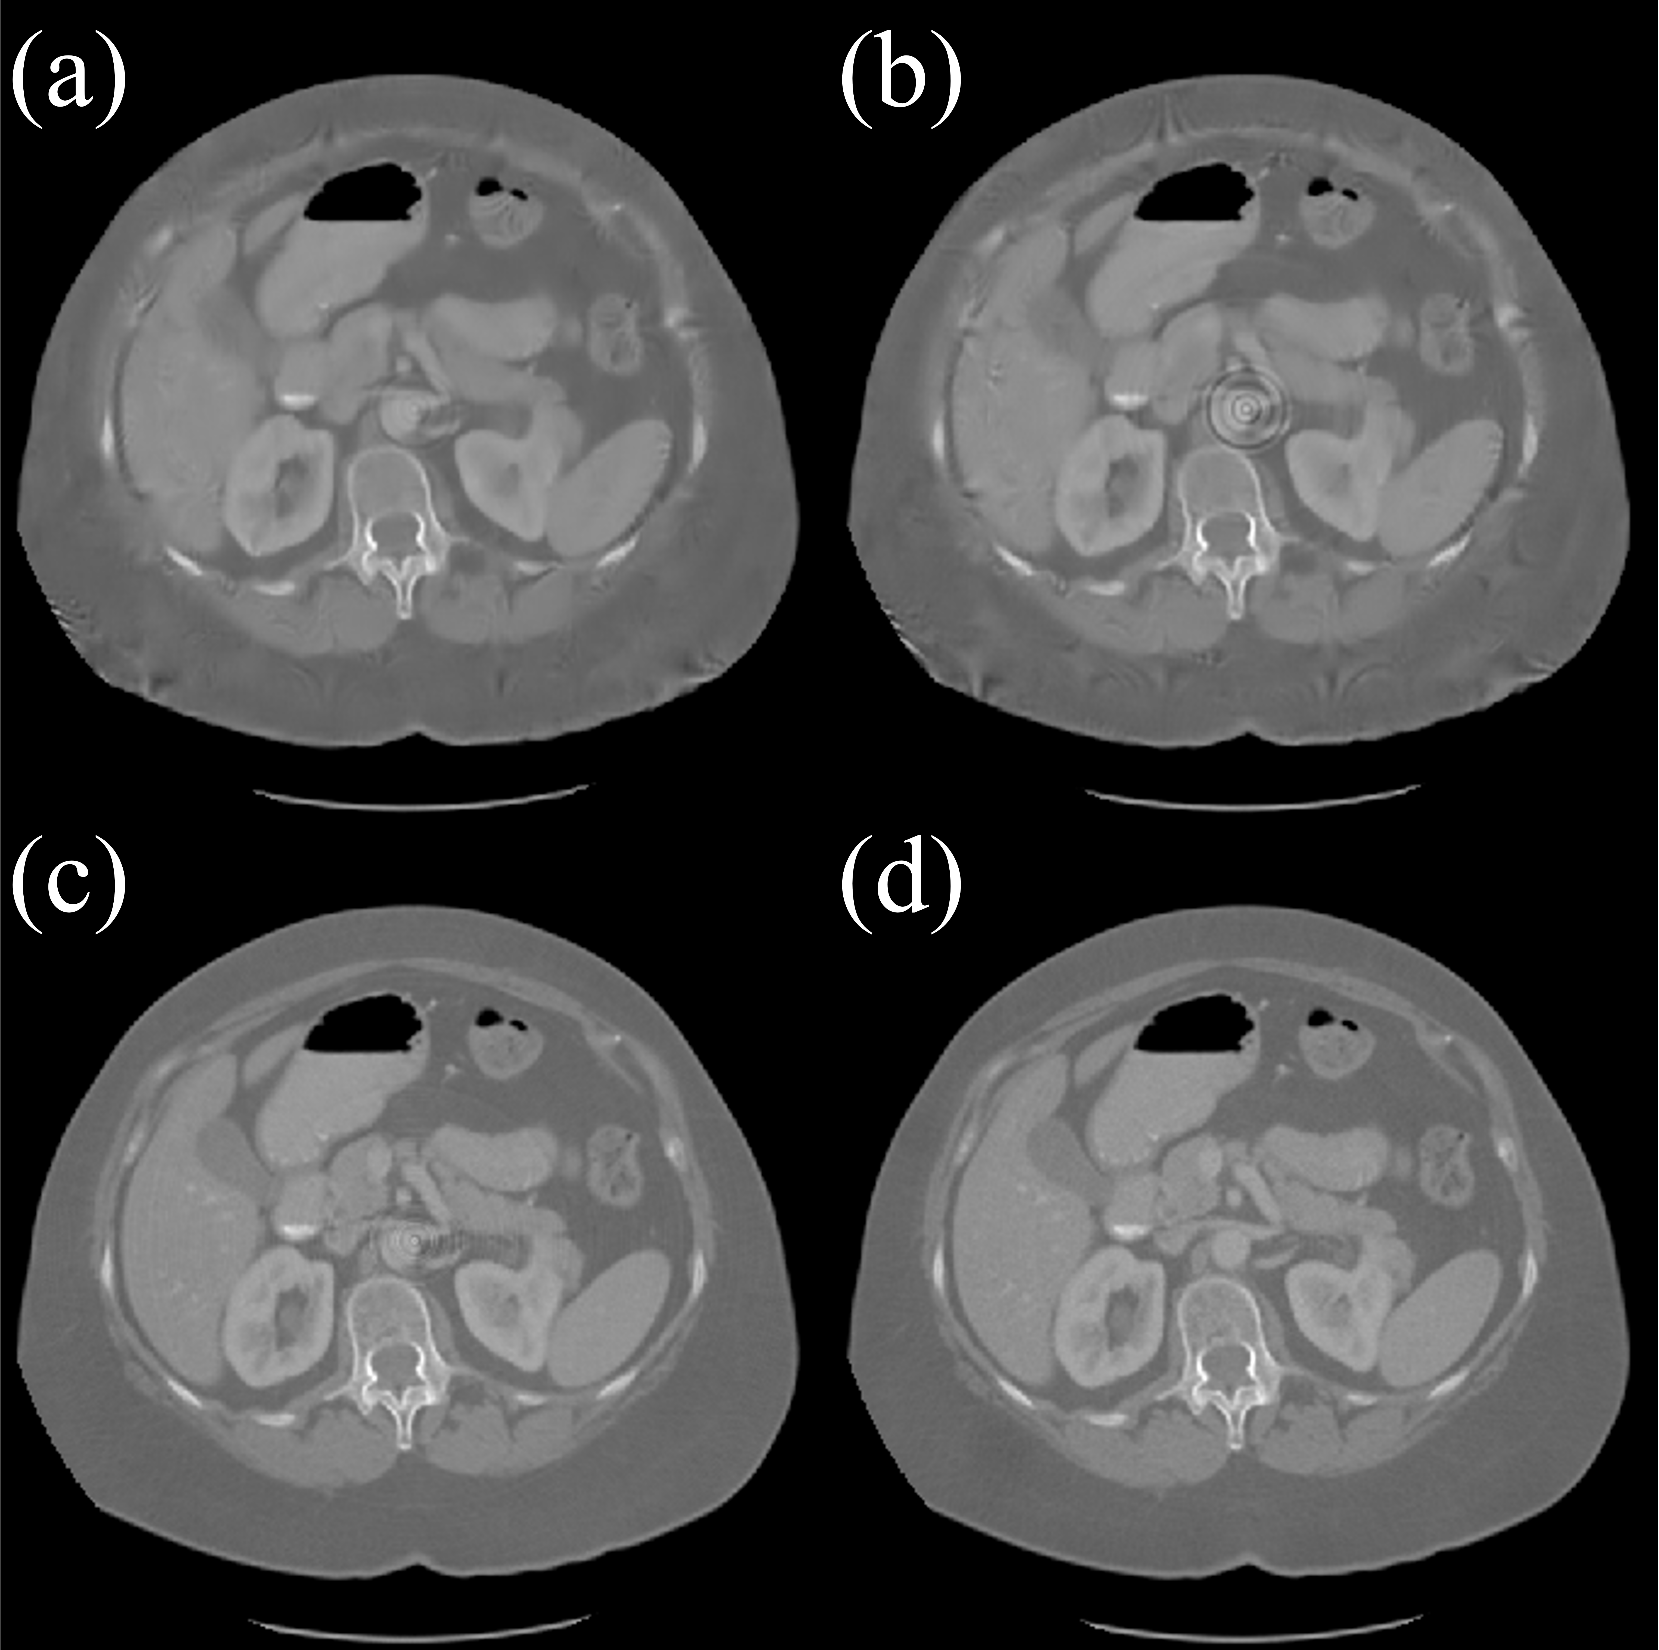

Refer to caption

Figure 8: Visual comparisons for 4 different testing datasets. The CT images are having unit of HU values. First column: MMWHS, second column: RibFrac, third column: RIRE, and last colum: LDCT (from left to right).